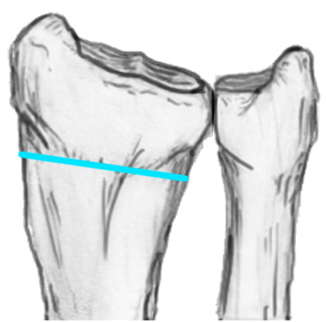

Radial angles

| Volar tilt mean 11° | Radial inclination mean 22° | Radius mean 11 mm longer than ulna |